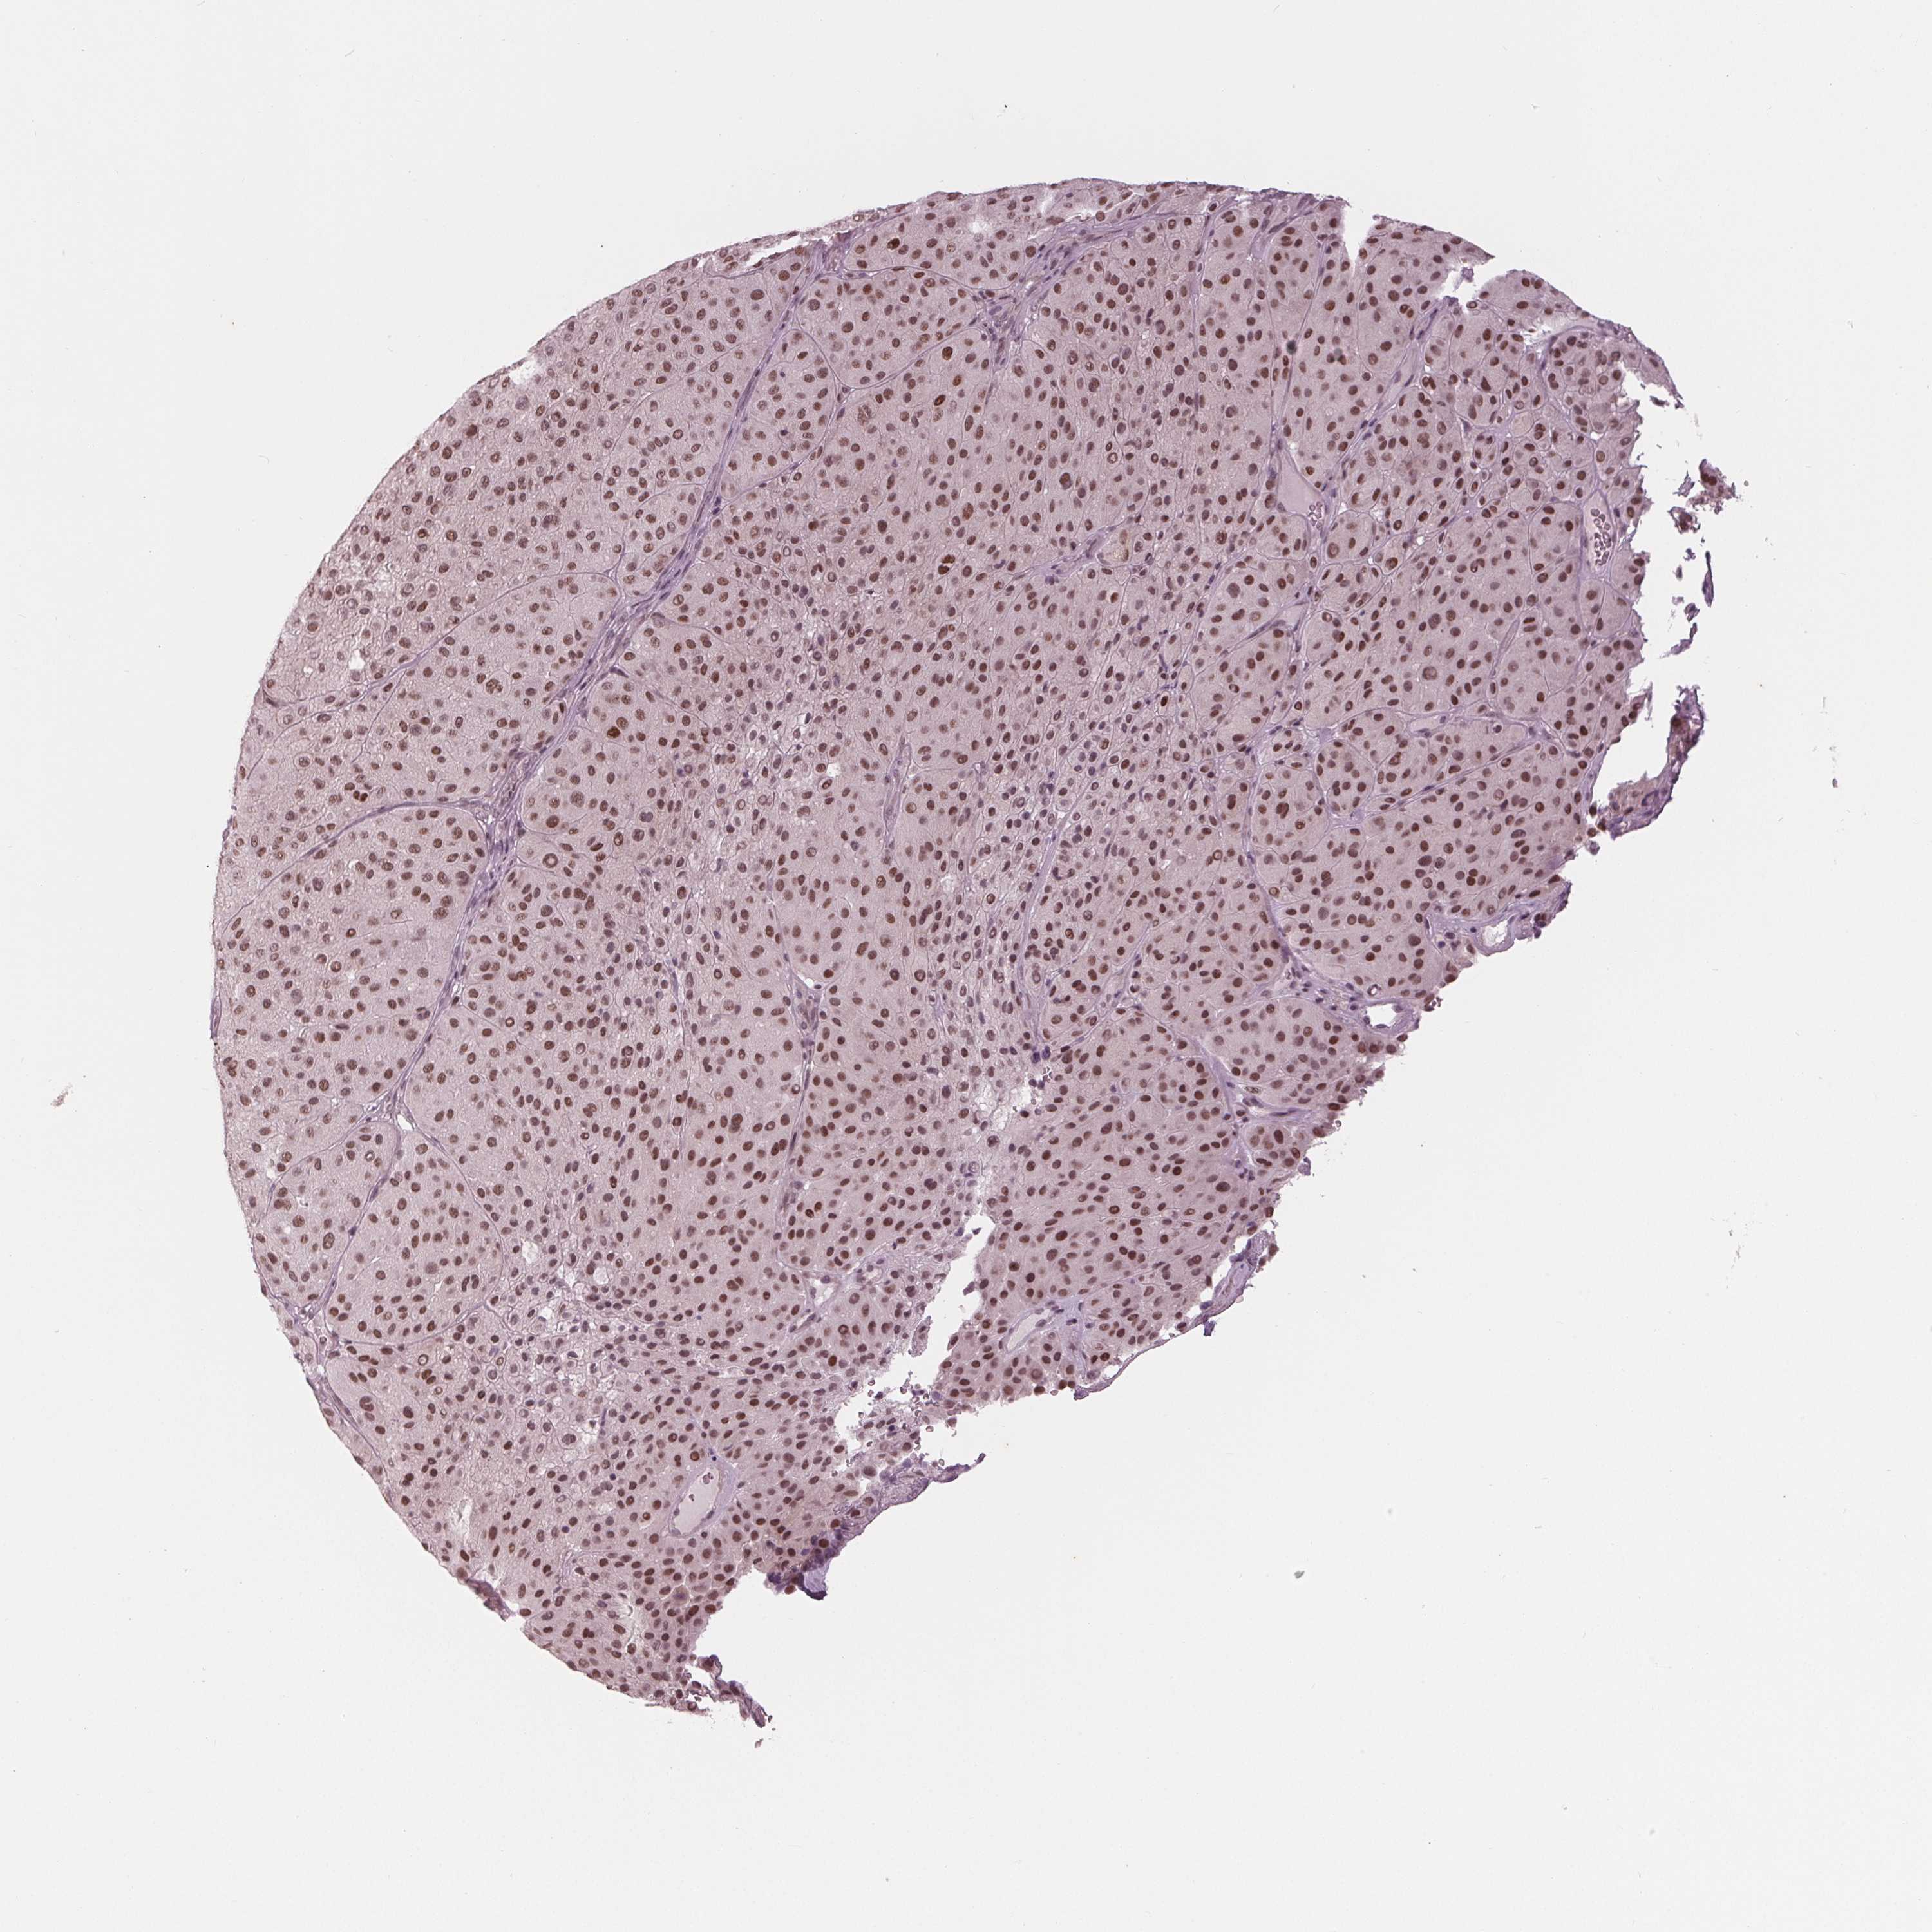

MELANOMA - Protein expressioni

A mouse-over function shows sample information and annotation data. Click on an image to view it in a full screen mode. Samples can be filtered based on level of antibody staining by selecting one or several of the following categories: high, medium, low and not detected. The assay and annotation is described here.

Note that samples used for immunohistochemistry by the Human Protein Atlas do not correspond to samples in the TCGA dataset.

Antibody stainingi

Antibody staining in the annotated cell types in the current human tissue is reported as not detected, low, medium, or high, based on conventional immunohistochemistry profiling in selected tissues. This score is based on the combination of the staining intensity and fraction of stained cells.

Each image is clickable and will lead to virtual microscopy that enables deeper exploration of all samples and also displays staining intensity scores, fraction scores and subcellular localization as well as patient and tissue information for each sample.

Antibody HPA066780

Staining

High

Medium

Low

Not detected

Intensity

Strong

Moderate

Weak

Negative

Quantity

>75%

75%-25%

<25%

None

Location

Nuclear

Cytoplasmic/membranous

Cytoplasmic/membranous,nuclear

Malignant melanoma, NOS

Malignant melanoma, Metastatic site